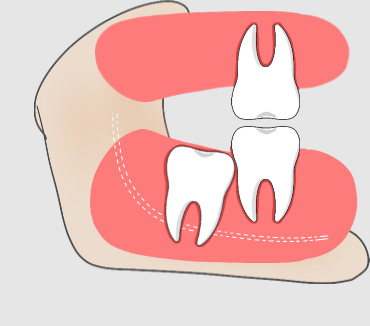

什么是无对咬牙?

智齿没有对咬牙一般指相对的两颗智齿中只有一颗长出来的情况建议及时拔掉。

无对咬牙的危害

如果智齿的对面没有相抗衡的智齿来对咬的话,有时会发生智齿过度萌发伸长的现象,进而影响咬合,此时应拔除智齿。